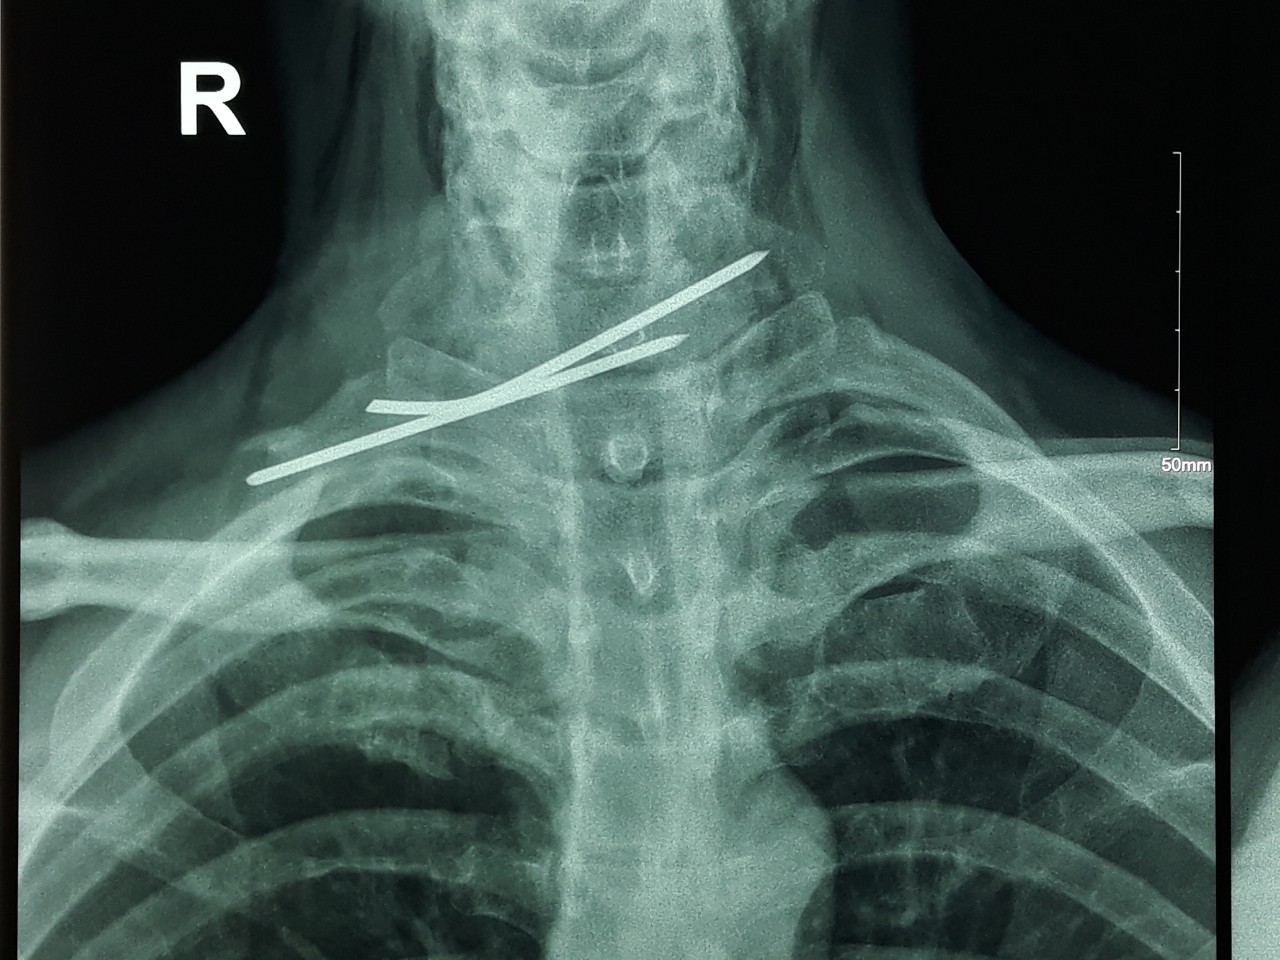

Hy hữu đinh cố định xương đâm xuyên thực quản, khí quản